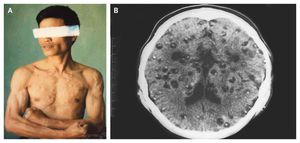

A 42-year-old man presented with seizures and approximately 300 palpable intramuscular cysts, with 54 cysts on his head, face, and neck, 110 on his chest and back, 86 on his arms, and 52 on his legs (Panel A). During the 3 years preceding presentation, he reported having a chronic headache and witnessing the development of intramuscular cystic nodules on his arms and his upper body (measuring 0.5 to 0.7 cm in diameter and 0.5 to 2.0 cm in diameter, respectively). Proglottids could be seen in his feces. A subcutaneous biopsy was performed, and a scolex with suckers and hooklets typical of the tapeworm Taenia solium were detected. A cranial computed tomographic scan was obtained and showed numerous neurocysticercosis cysts (measuring 3 to 5 mm in diameter) in his brain, containing living, dead, calcified, and mummified forms of the parasite (Panel B). The patient was given a single dose of praziquantel on the first day, followed by three rounds of treatment with albendazole administered for 30 days, withheld for 10 days, and then restarted. After 4 months of treatment, his headaches and seizures resolved, and resolution of the cysts could be seen on magnetic resonance imaging. The patient has recovered and has reported having no further seizures. source: nejm.org